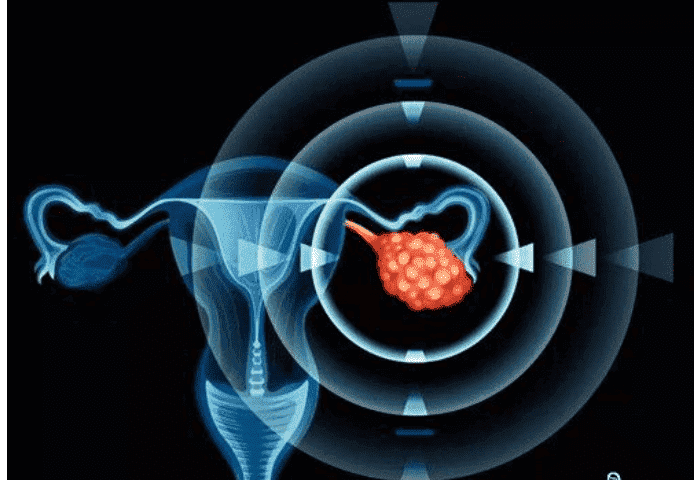

| 宫外孕病因一 | 输卵管炎症

| 宫外孕病因二 | 输卵管手术史或输卵管发育不良

| 宫外孕病因三 | 有宫外孕病历史

| 宫外孕病因四 | 上过避孕环

| 宫外孕病因五 | 受精卵游走

| 宫外孕病因六 | 受精卵游走

得宫外孕的6种病因